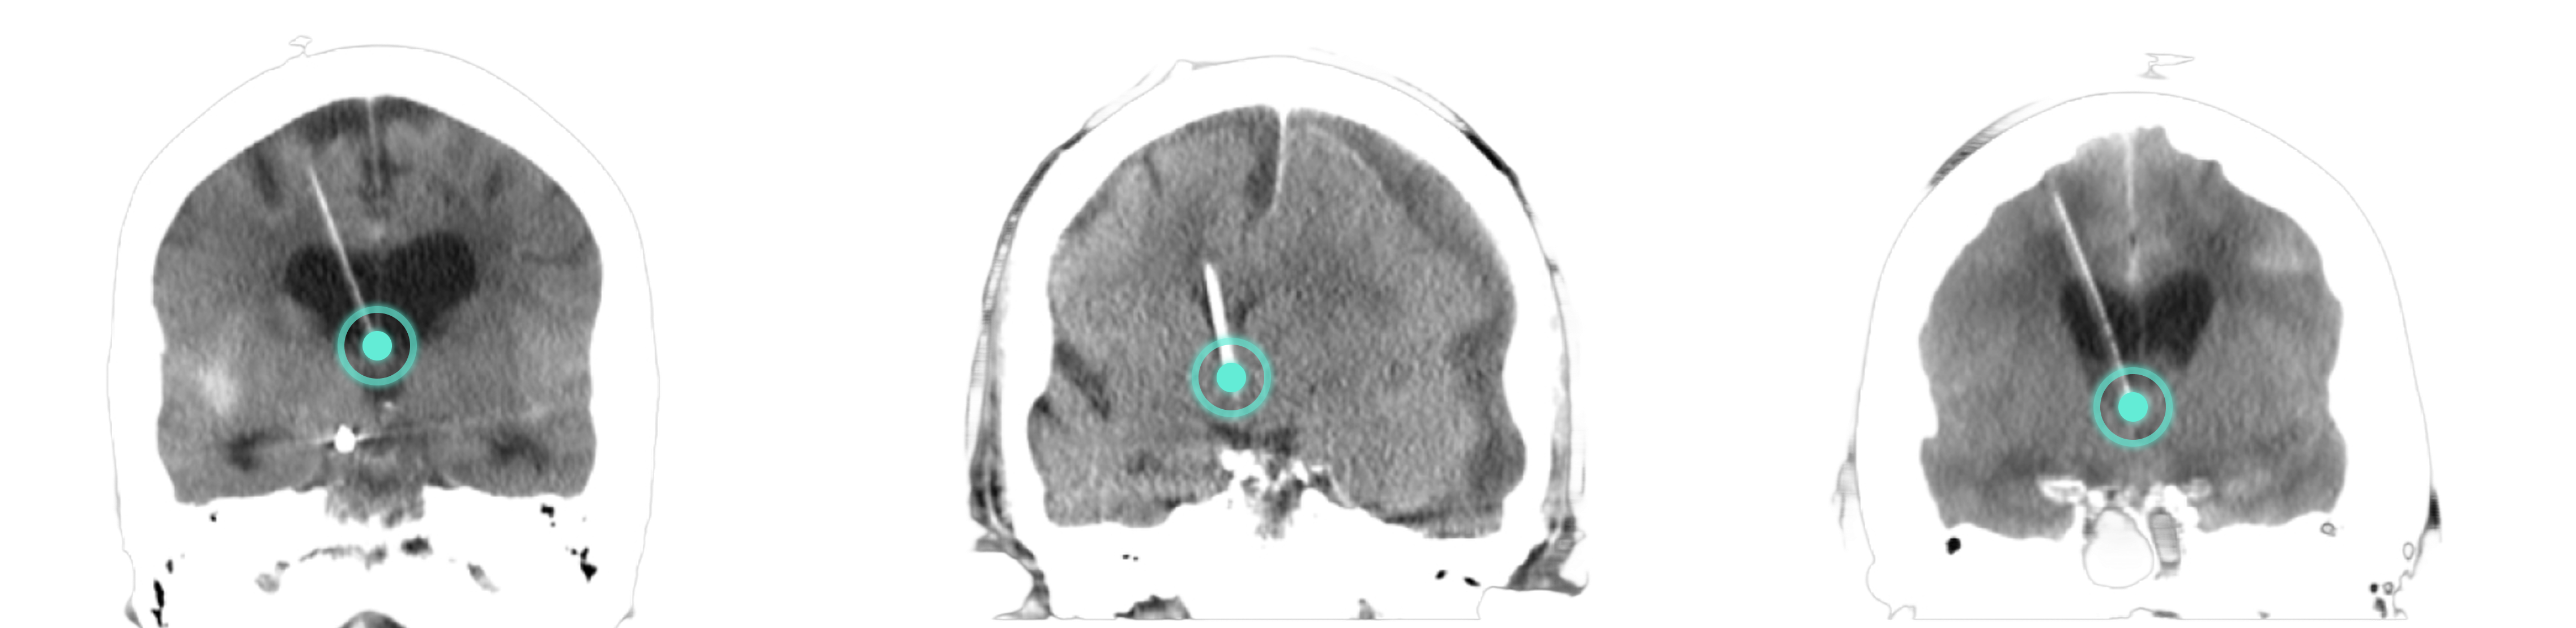

Cranial Navigation

FDA cleared AR system

for Cranial Navigation

5X improved accuracy